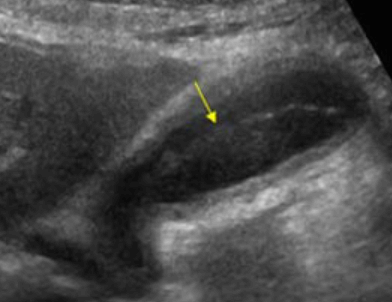

US finding

- 담낭이 비대해지고 담낭벽이 비후 된다

- 담낭 내 격막이 있다